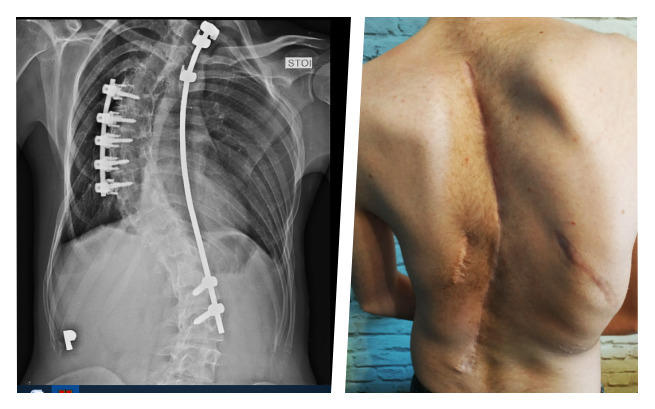

Choroba początkowo była dla mnie zagadką, kiedy zdiagnozowano skoliozę idiopatyczną miałem 14 lat. Niestety, od tego czasu cierpienie wpisane jest w moją codzienność, a ból bywa nie do zniesienia…

Dziś mam 23 lata. Moi rówieśnicy podejmują kolejne wyzwania. Dla mnie jednym z największych jest podniesienie się z łóżka i wykonanie najprostszych czynności. Skolioza skutecznie utrudnia mi funkcjonowanie, a postępujące skrzywienie wpływa nie tylko na postawę, ale pracę całego organizmu, bo kręgosłup coraz bardziej uciska narządy wewnętrzne.

Dotychczasowe operacje nie przyniosły rezultatu, a ja zostałem sam na sam z moim bólem i rosnącym przerażeniem. Mam wrażenie, że czas mi się kończy, bo wszystko zawiodło, a choroba coraz bardziej brutalnie odbiera mi możliwości… W tym momencie muszę postawić wszystko na jedną kartę i działać, by ratować się przed kolejnymi tragicznymi konsekwencjami!